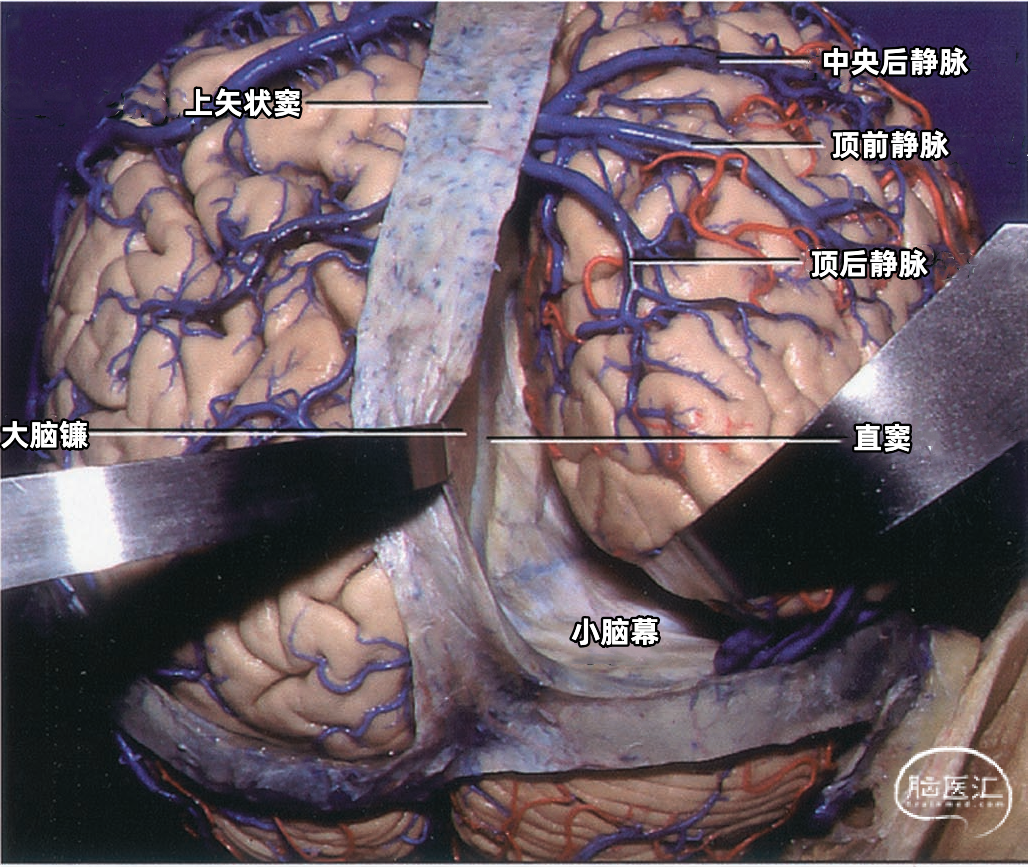

下图示右侧中央后静脉、顶前静脉,顶后静脉汇入上矢状窦。没有桥静脉汇入上矢状窦后部。抬起右侧枕叶显露小脑幕,大脑镰和直窦。在枕极和上矢状窦、直窦之间没有桥静脉。

下矢状窦(inferior sagittal sinus 下图)夹于大脑镰游离缘中,前方起自盲孔,向后注入直窦。下矢状窦直径为2mm左右,最短者仅19mm,长者可达110mm,平均长度70mm,其腔内无蛛网膜颗粒。主要收集大脑镰、胼胝体和扣带回附近的静脉血。

▼6.直窦

直窦(straight sinus)位于大脑镰与小脑幕的连接处(下图),起源于胼胝体压部后方,由下矢状窦与大脑大静脉(Galen静脉)汇合而成,汇合处管径膨大,向后于枕内隆凸处注入窦汇。直窦平均长约50mm,呈尖端向上的三角形。此窦多数是下矢状窦的直接延续。大脑大静脉是汇入直窦的最大静脉。直窦向后除注入窦汇外,尚可直接注入横窦,它可以进入任何一侧的横窦,但多数主要汇入左侧的横窦。

每侧小脑幕有两个恒定但不对称的静脉窦,即内侧小脑幕窦和外侧小脑幕窦。 内侧小脑幕窦由小脑上表面的回流静脉汇聚而成。内侧小脑幕窦向内侧引流入直窦,或直窦与横窦的汇合处。 外侧小脑幕窦由颞叶和枕叶基底面和外侧面的回流静脉汇聚而成。外侧小脑幕窦起自小脑幕的外侧部分,并向外侧引流入横窦的末端。 下图示抬起小脑幕,可见来自小脑、在小脑幕下缘入窦的桥静脉。左侧黄色箭头显示一支较大的静脉自小脑上表面进入内侧小脑幕窦。右侧红色箭头显示一支粗大的来自小脑上表面的桥静脉在窦汇前方进入内侧小脑幕窦。